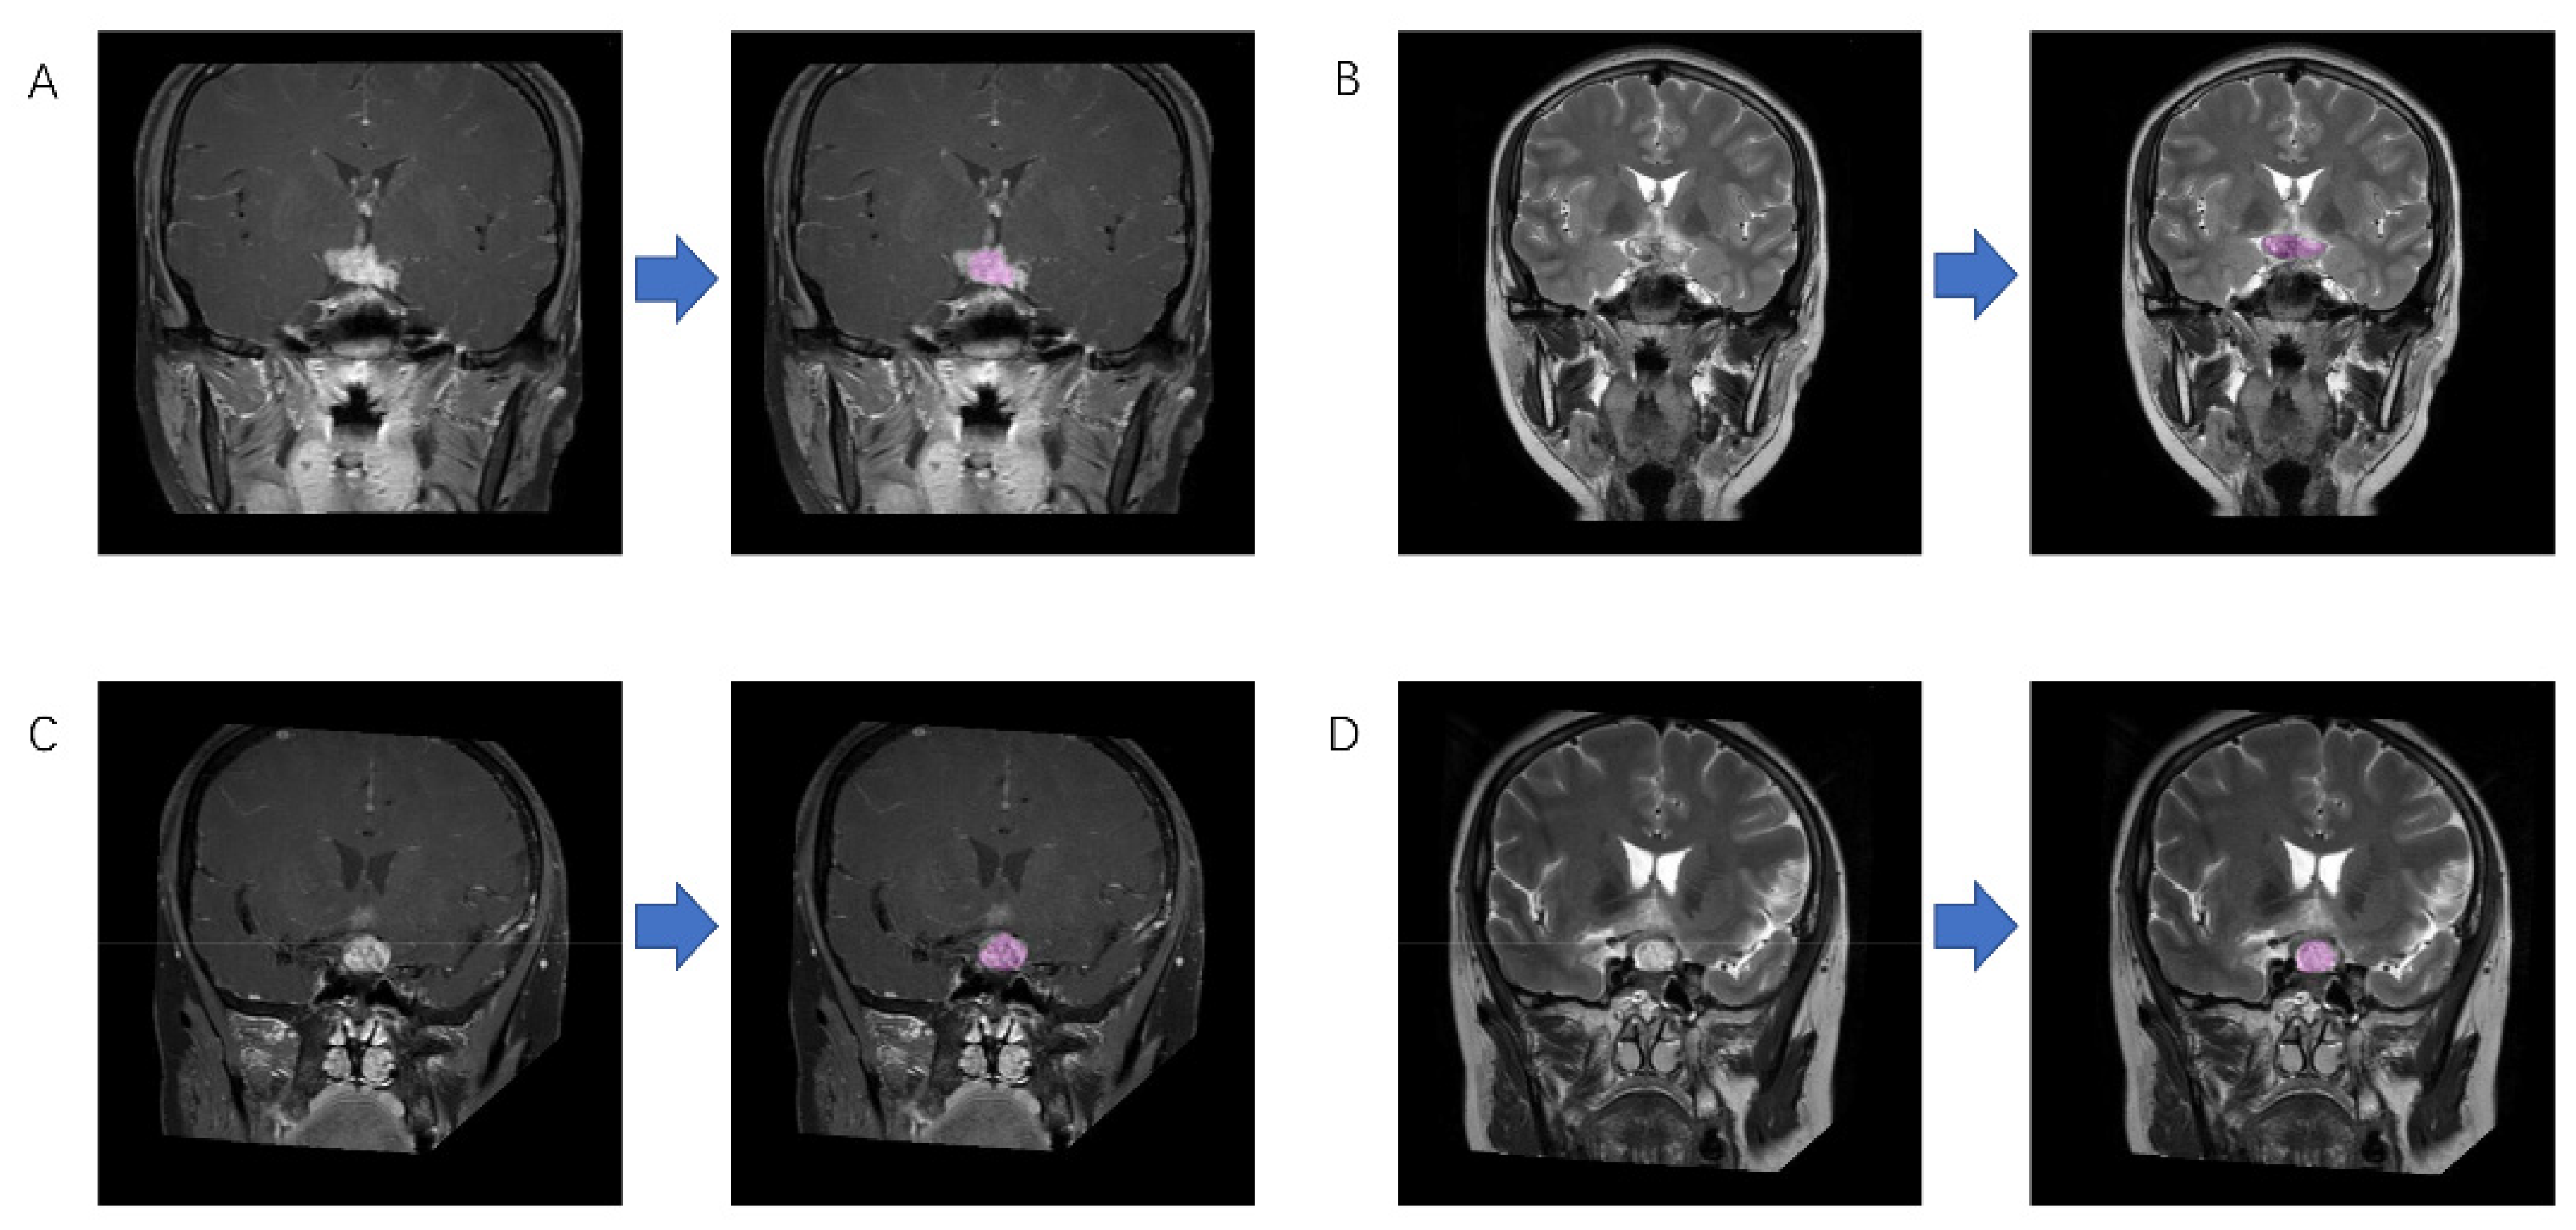

2.3. Radiomic Feature Extraction

Two neurosurgeons participated in the extraction of radiomic features using LifeX package (http://www.lifexsoft.org accessed on 6 December 2020) and following the instructions on the website [23]. With the supervision of a senior radiologist with 10 years of experience, the regions of interest (ROI) were drawn along the boundary of the lesions slice-by-slice to obtain three-dimensional radiomic features (Figure 2). Clear cystic components were not included in the ROI since the signal strength of MRI varies with the composition of the cystic contents. Any disagreement on the segmentation was solved by consensus or by the senior radiologist.

Figure 2. Example of region of interest drawing. This figure shows magnetic resonance imaging of (A) germinoma on contrast-enhanced T1WI; (B) germinoma on T2WI; (C) craniopharyngioma on contrast-enhanced T1WI; (D) craniopharyngioma on T2WI before and after drawing.